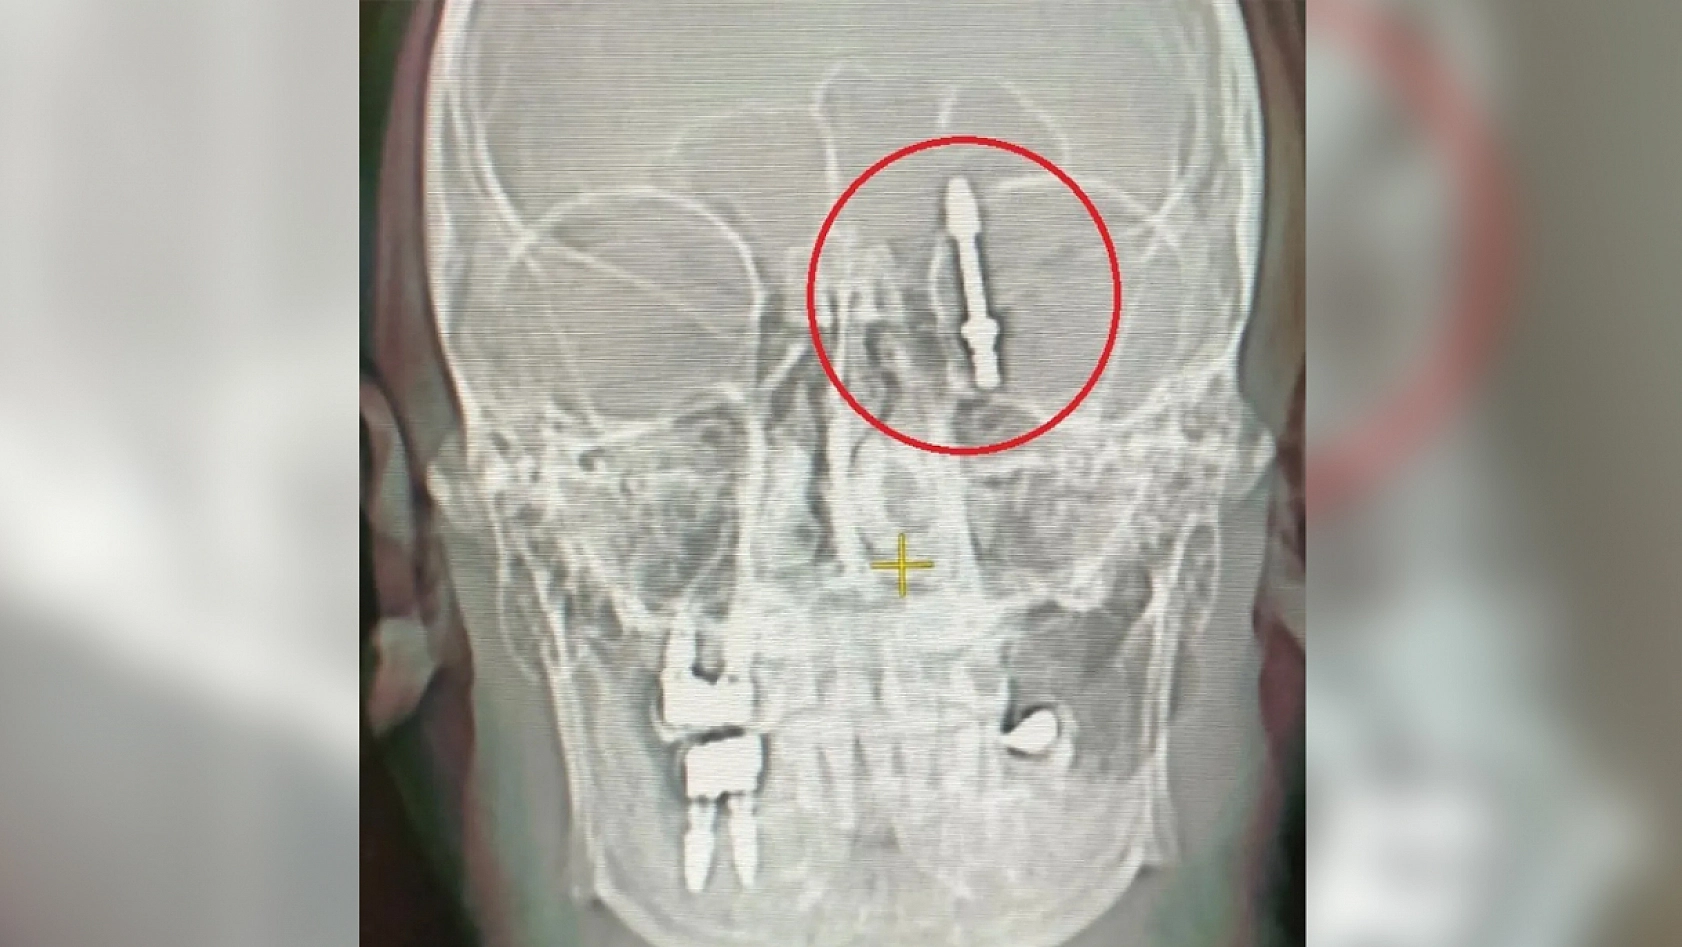

Diş tedavisi felakete dönüştü: İmplant vidası kafatasına saplandı

Bursa'da özel bir diş kliniğinde implant tedavisi sırasında yaşanan talihsiz olayda, implant vidası çene kemiğini delip kafatasına kadar ilerledi. Talihsiz hasta saatler süren ameliyatla ölümden dönerken, iki yıldır adalet mücadelesi veriyor.